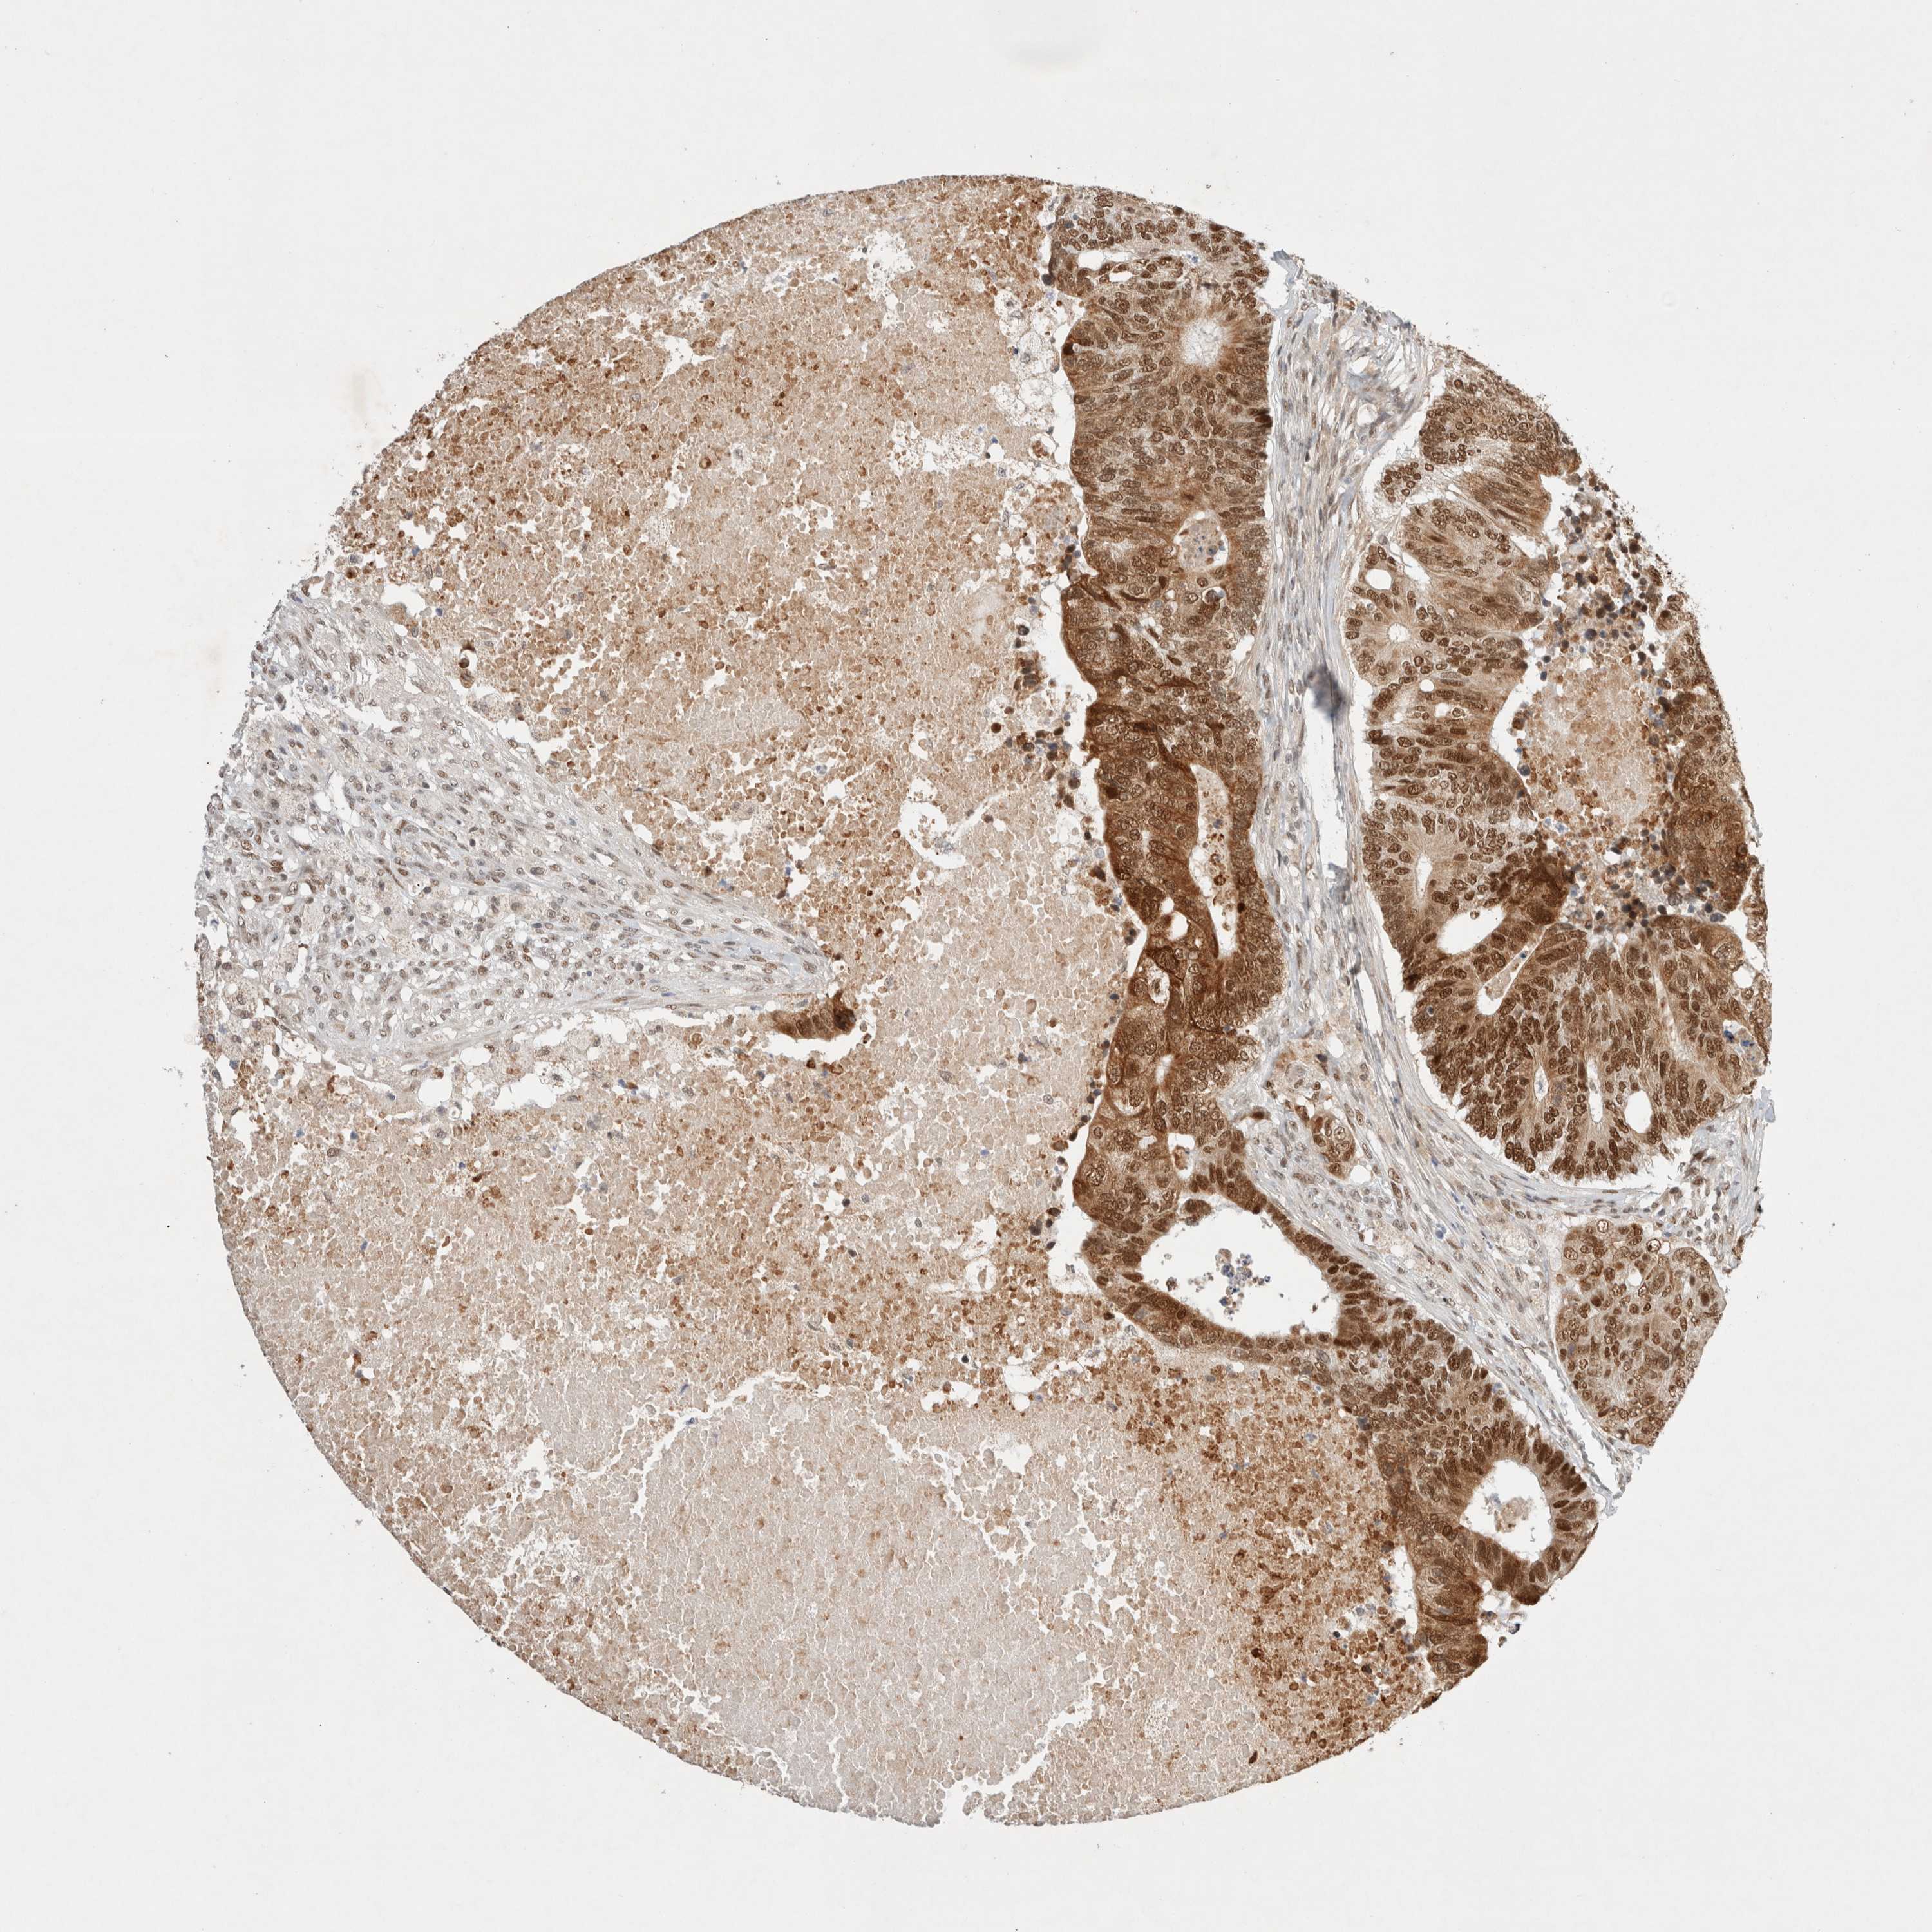

CANCER COLORECTAL CANCER Show tissue menu

Colorectal cancer

Human cancer

Colon adenocarcinoma